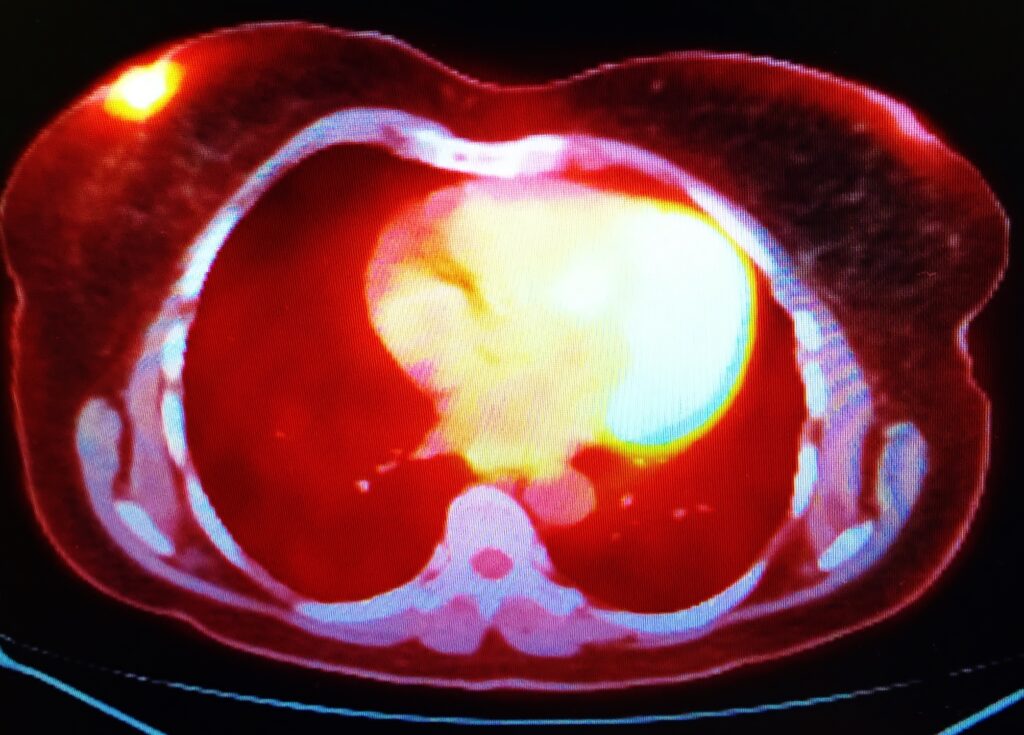

- Diagnostics: Imaging procedures using tracers like FDG to visualise metabolic activity.

- Positron Emission Tomography (PET) Scanners: Detect positrons emitted during radiotracer decay and create highly detailed images.

- Hybrid Systems (PET-CT, SPECT-CT): Combine functional imaging with anatomical data for improved diagnosis.

For example, in a case of suspected lung cancer:

- Clinical Problem: Determining the presence and extent of the tumour.

- Radiopharmaceutical: Administering Fluorine-18 FDG to highlight cancerous cells.

- Instrumentation: Using a PET-CT scanner to obtain precise images.